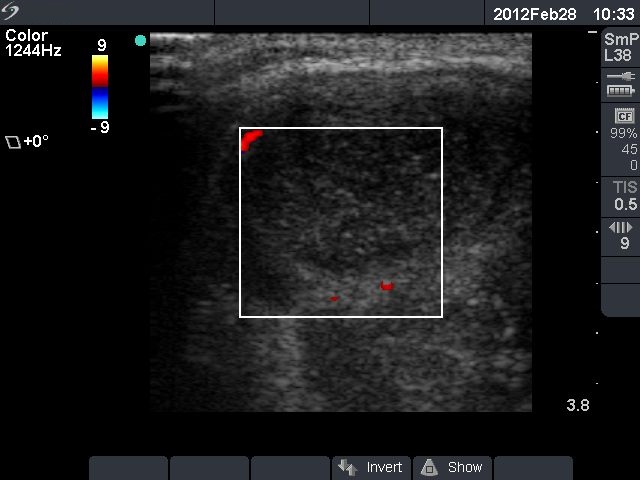

First row: ultrasonographic picture before sclerotherapy. The size of the lesion was 38x28x39 mm (width x depth x length).